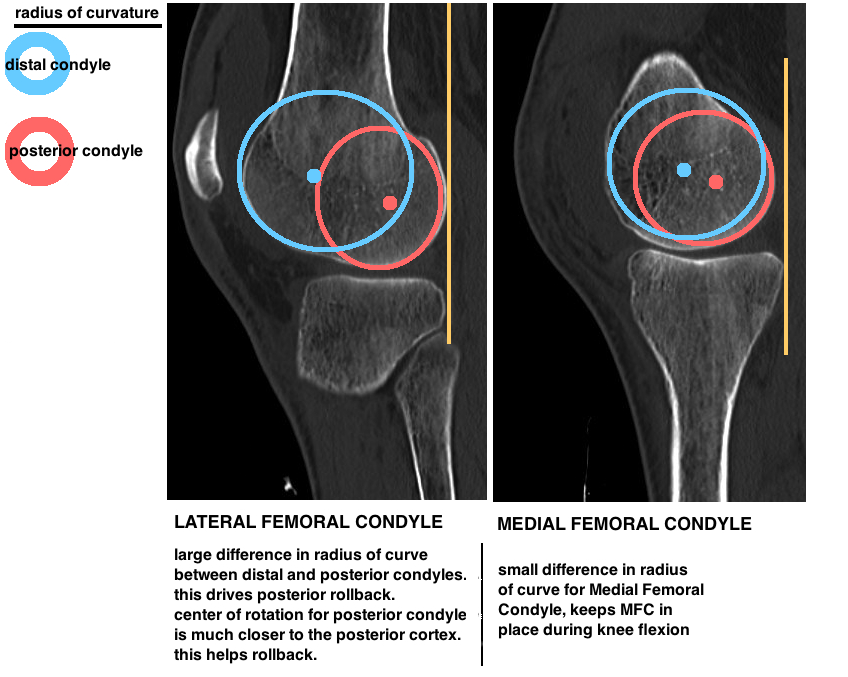

• Native Knee Kinematics Hip Knee Book